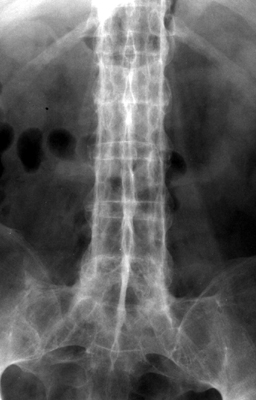

Trolley-track Sign

Ankylosing Spondylitis

Single radiograph of the lumbar spine with linear vertical increased density along the spinous processes. This single central radiodense line on frontal radiographs is related to ossification of supraspinous and interspinous ligaments. In addition, there are two more lateral vertical linear lines, which represent ossification of the apophyseal joint capsules. The three vertical ossified lines together make up the trolley-track sign.